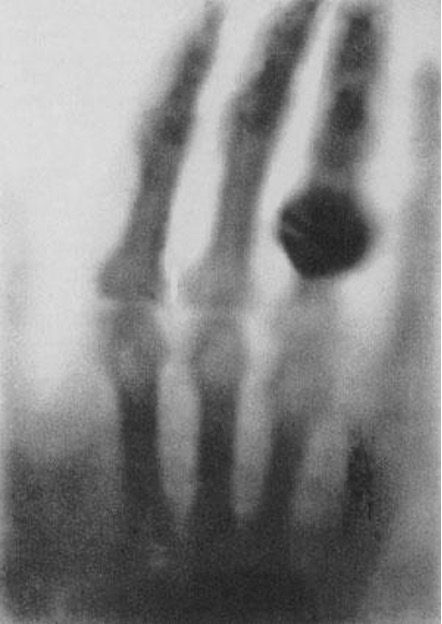

En 1895, Wilhelm Roentgen descubrió los rayos X, lo que transformó el hospital de un lugar donde la gente iba a morir, a un recinto donde se podían realizar tratamientos y diagnósticos para curar enfermedades.

r radiografía realizada, mano de Anna Roentgen, 198

Desde ese momento, el equipamiento médico ha ido desarrollándose de manera exponencial, ya que cada vez más el diagnóstico de pacientes y el tratamiento de enfermedades se apoyan en la imagen. Los equipos médicos más relevantes en la actualidad son los utilizados en los servicios de diagnóstico por imagen, radioterapia y cirugía, además de los sistemas de inteligencia artificial adaptativos en salud.